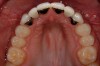

Figure 3 Additional orthodontic treatment is initiated to improve the dental midline and evenly distribute the space around the microdontic lateral incisors.

Figure 3

Figure 4 The dental midline is in improved harmony with the facial midline following the second round of orthodontic treatment.

Figure 4